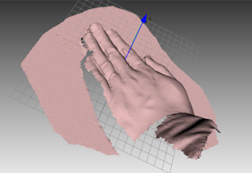

使用事例: 整形美容外科

美容整形を希望する患者にとって自分自身が、術後どのような姿に変わるのか大いに気になり、心配するところです。患者は術後の様子を他患者の例で紹介されることがあると聞きますが、はやり自分がどのように変貌するか前もって確認したいところです。その場合、術後の自分を3Dで見ながら説明を受けると、どう変貌するか容易に理解できます。例えば、術後にどのぐらい鼻が高くなり、または しわが減るのか、あるいは二重まぶたや顎が横からどのように見られるのか、術前に確認できます。そのためには最初に術前の姿を3D計測し、このモデルを元に術後の姿を、担当医と相談しながら決めていくことができます。

術前の姿を高精度で3Dモデルを作る機器としては、ハンディ3Dスキャナーが最適です。ハンディ3Dスキャナーはレーザーとは異なり、写真撮影で三次元のモデルを作っていきます。そのため操作前のカリブレーションが不要で、またデータ合成用のマーカーも必要ありません。ちょうど「アイロンをかける」ようなイメージで、顔の周りを移動しながら計測していきます。顔の3Dモデルの作成時間は、計測も含めて約10分です。術後の姿を患者に前もって伝えることは、インフォームド・コンセントになります。

| 術前 |  |

| 術後の予測 |  |